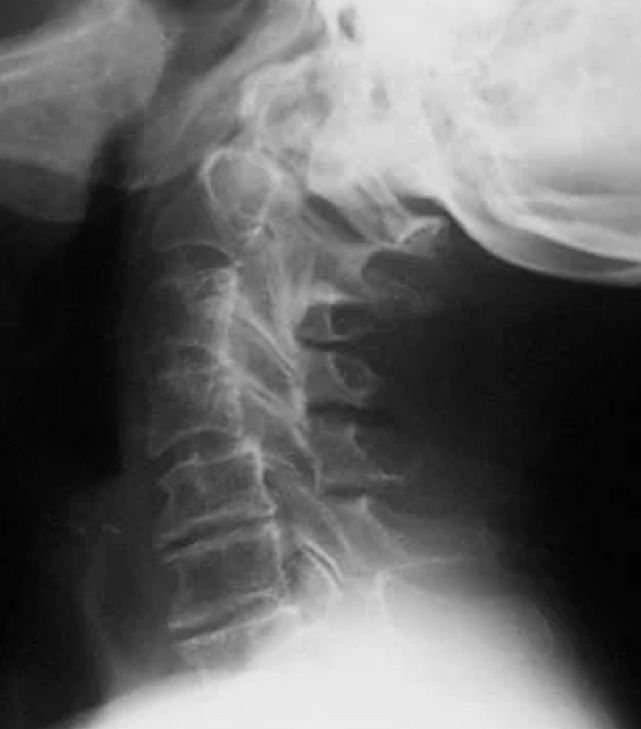

Phase III Cervical Spine

After years of neglect, the improperly functioning spinal joints often fuse together.

A lifetime of neglect may cause the eventual fusion of the malfunctioning joints. Atrophy permanent nerve damage, and soft tissue degeneration are prevalent. Reduced mobility and impaired nervous system function, diminish one's quality of life

This 75-year old patient prevented Subluxation Degeneration with many years of regular chiropractic checkups.